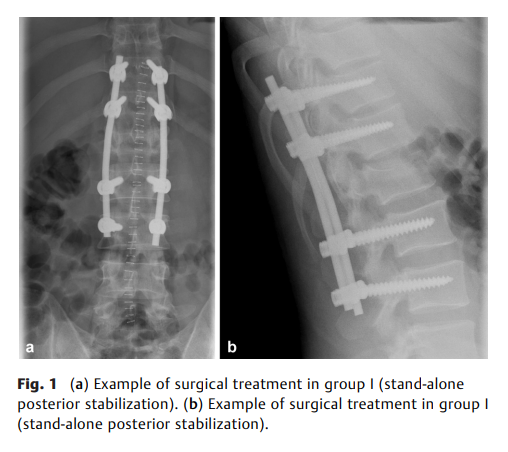

既往研究强调通过恢复矢状面序列和椎体高度来矫正脊柱骨折导致的畸形。本研究旨在比较创伤性胸椎或腰椎骨折手术治疗中,单纯后路稳定术(第一组)与后前路/联合入路(第二组)在影像学结果(包括矢状面指数和椎体高度丢失)方面的差异。

共纳入71例患者(男性42例),中位年龄38岁(四分位距:28–54),中位随访时间4个月(四分位距:3–17)。第一组32例,第二组39例。40例骨折位于胸腰段(T12或L1),15例位于胸椎,14例位于腰椎。回归模型显示,第二组在矢状面对线上更优,校正后矢状面指数平均差为–4.24(95%置信区间:–7.13至–1.36;p=0.004);联合入路在椎体高度恢复方面更具优势,校正后椎体高度丢失平均差为0.11(95%置信区间:0.02–0.20;p=0.02)。整个队列中共发生9例术后并发症(第一组4例,第二组5例)。

与单纯后路入路相比,采用前后路联合稳定术治疗脊柱骨折可通过改善矢状面序列、增加椎体高度来有效矫正畸形,且并发症发生率在可接受范围内。